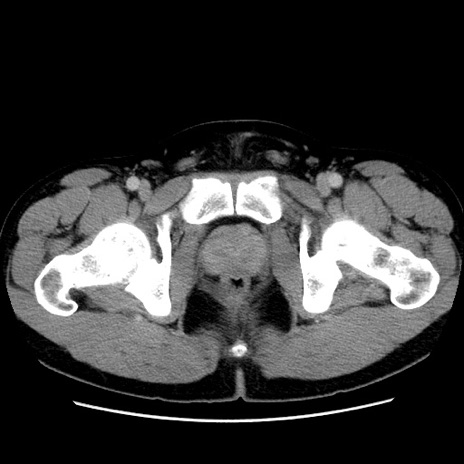

冠状断像

【症例】30歳代男性

【主訴】腹痛、嘔吐

【現病歴】昨晩から突然の腹痛あり、その後嘔吐、軟便も出現。腹痛が改善しないため救急搬送となる。2日前にしめ鯖の食事歴あり。

【身体所見】意識清明、苦悶様、BP 135/90mmHg、BT 35.7℃、腹部:平坦、やや硬、心窩部〜臍部に自発痛、圧痛あり、筋性防御+、反跳痛-

【データ】WBC 8100、CRP 0.57